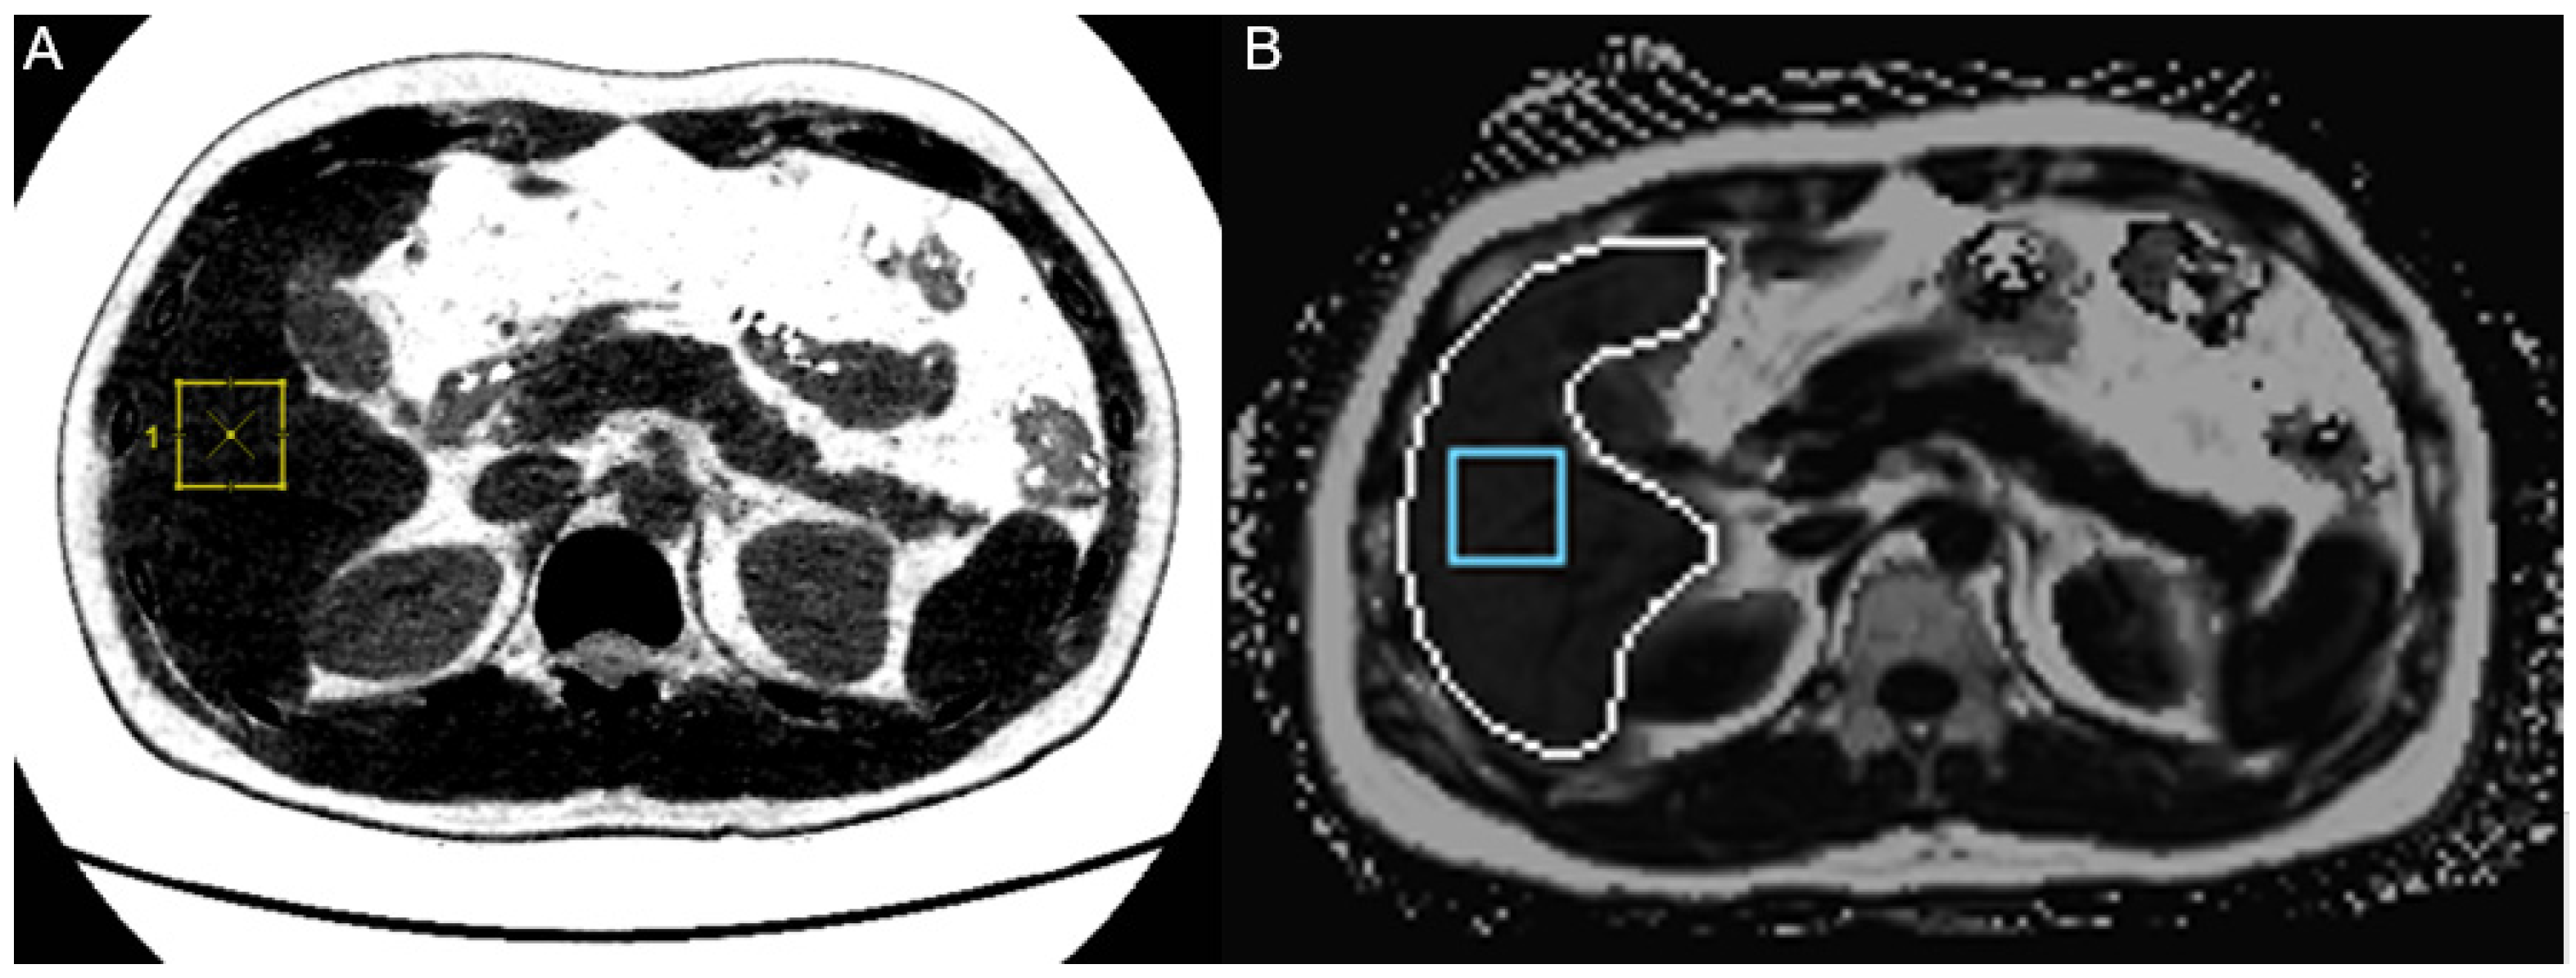

2.3. Data Analysis